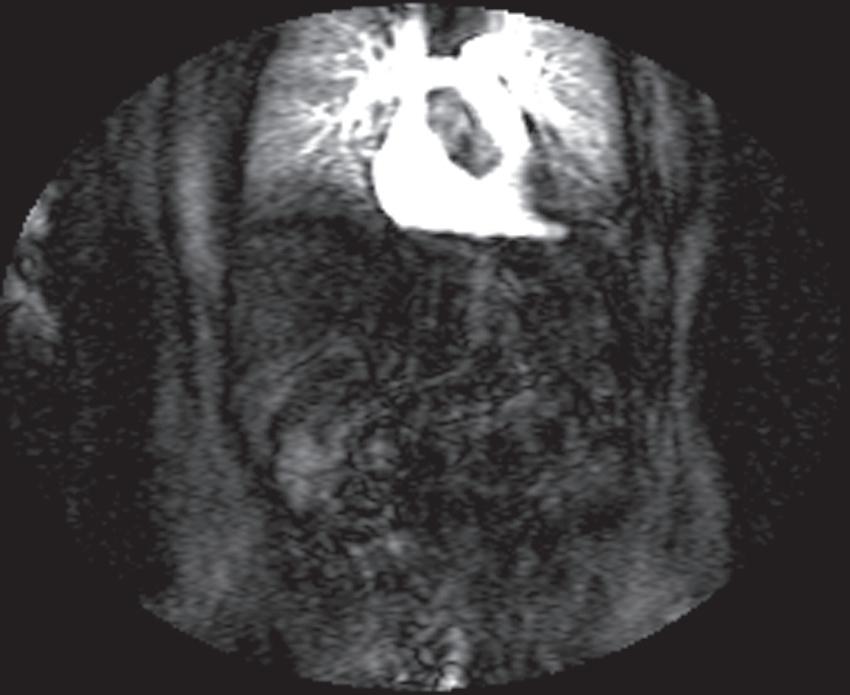

Real-time viewing of contrast transit (Bolus Track, Philips; CARE Bolus, Siemens; SmartPrep, GE; VisualPrep, Toshiba) involves careful monitoring by the technologist of serial large field-ofview (FOV) GE images after administration of the entire bolus of contrast (see Fig. 1.17). Transit of gadolinium through the superior vena cava (SVC) into the right heart through the pulmonary circulation and from the left heart into the aorta is portrayed on the monitor cinegraphically. With impending arrival of contrast into the abdominal aorta, the technologist instructs the patient to suspend respiration in preparation to acquire the arterial phase images. Portal phase images (or

FIG. 1.17 Example of Bolus Track timing sequence to initiate the dynamic acquisition. Selected serial coronal large field-of-view gradient-echo images obtained immediately after the intravenous administration of gadolinium (A–D) reveal the inflow of gadolinium into the superior vena cava (SVC; A), the right ventricle (B), through the pulmonary outflow tract and into the pulmonary arterial system (C), and into the thoracic aorta, down the abdominal aorta (D).